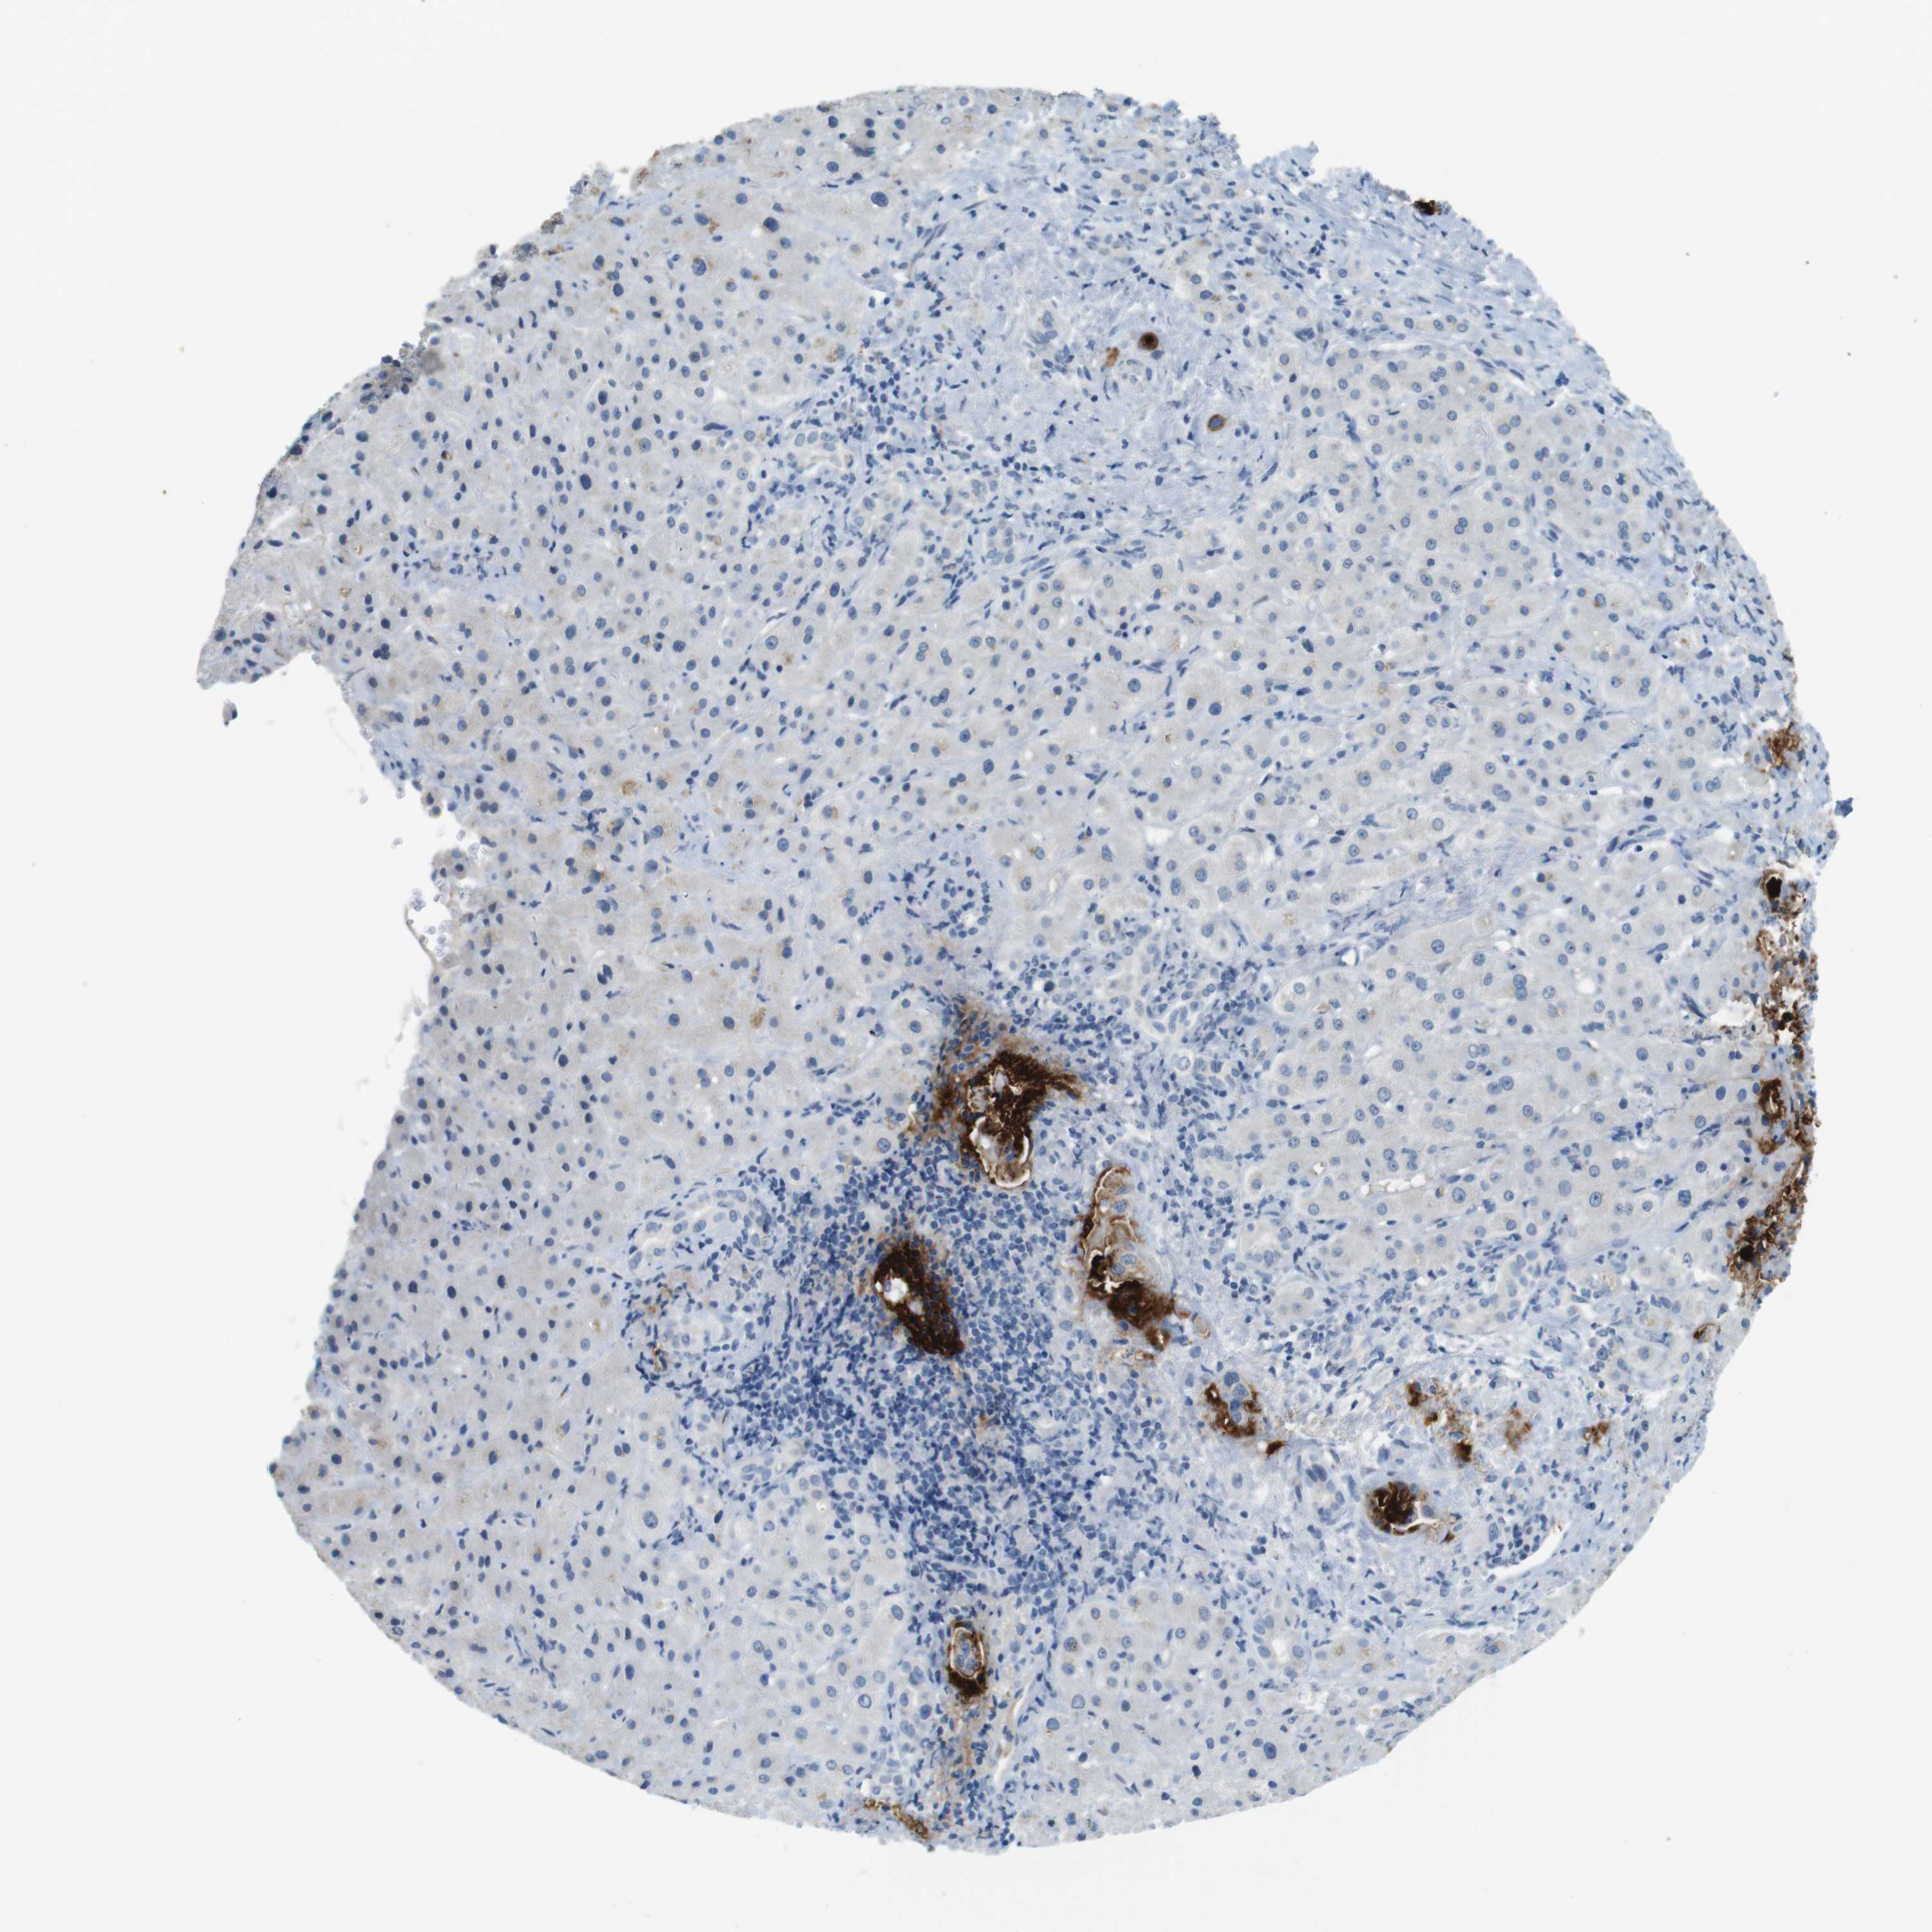

LIVER CANCER - Protein expressioni

A mouse-over function shows sample information and annotation data. Click on an image to view it in a full screen mode. Samples can be filtered based on level of antibody staining by selecting one or several of the following categories: high, medium, low and not detected. The assay and annotation is described here.

Note that samples used for immunohistochemistry by the Human Protein Atlas do not correspond to samples in the TCGA dataset.

Antibody stainingi

Antibody staining in the annotated cell types in the current human tissue is reported as not detected, low, medium, or high, based on conventional immunohistochemistry profiling in selected tissues. This score is based on the combination of the staining intensity and fraction of stained cells.

Each image is clickable and will lead to virtual microscopy that enables deeper exploration of all samples and also displays staining intensity scores, fraction scores and subcellular localization as well as patient and tissue information for each sample.

Antibody HPA008246

Antibody CAB009396

Cholangiocarcinoma

Carcinoma, Hepatocellular, NOS